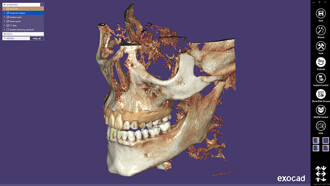

Exocad’s first international congress hailed a success

DARMSTADT, Germany: Dental software company exocad recently hosted its first international congress, exocad Insights. With over 550 attendees from more than...